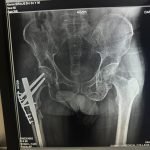

- Hip Replacement Surgery